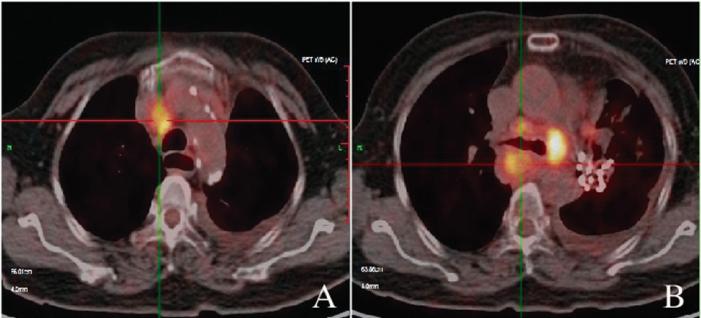

2019年3月21日患者转入放疗科第2天即出现喘息,经抗炎解痉等对症支持治疗未见明显缓解,后通过检查显示,1、左肺门符合粒子植入术后改变,边缘代谢略增高,考虑肿瘤活性残留;左肺上叶支气管开口高代谢结节,为中心型肺癌,远端阻塞性部分肺不张;2、双侧肺门及纵膈多发淋巴结转移癌,部分病灶与相邻血管分界欠清;3、双侧胸腔积液,心包积液。计划尽快给予胸部放疗,靶区包括大体肿瘤体积:左肺病灶、双侧肺门和纵膈内肿大淋巴结。

(患者放疗前CT影像)